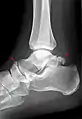

Ankle

Accessory bones at the ankle mainly include:

- Os subtibiale, with a prevalence of approximately 1%.[14] It is a secondary ossification center of the distal tibia that appears during the first year of life, and which in most people fuses with the shaft at approximately 15 years in females and approximately 17 years in males.[14]

- Os subfibulare, with a prevalence of approximately 0.2%.[15]

Os trigonum (further described below) may also be seen on an ankle X-ray.